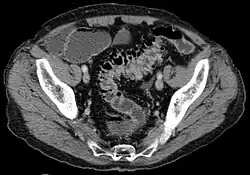

CT scan showing extensive diverticulosis of the sigmoid colon